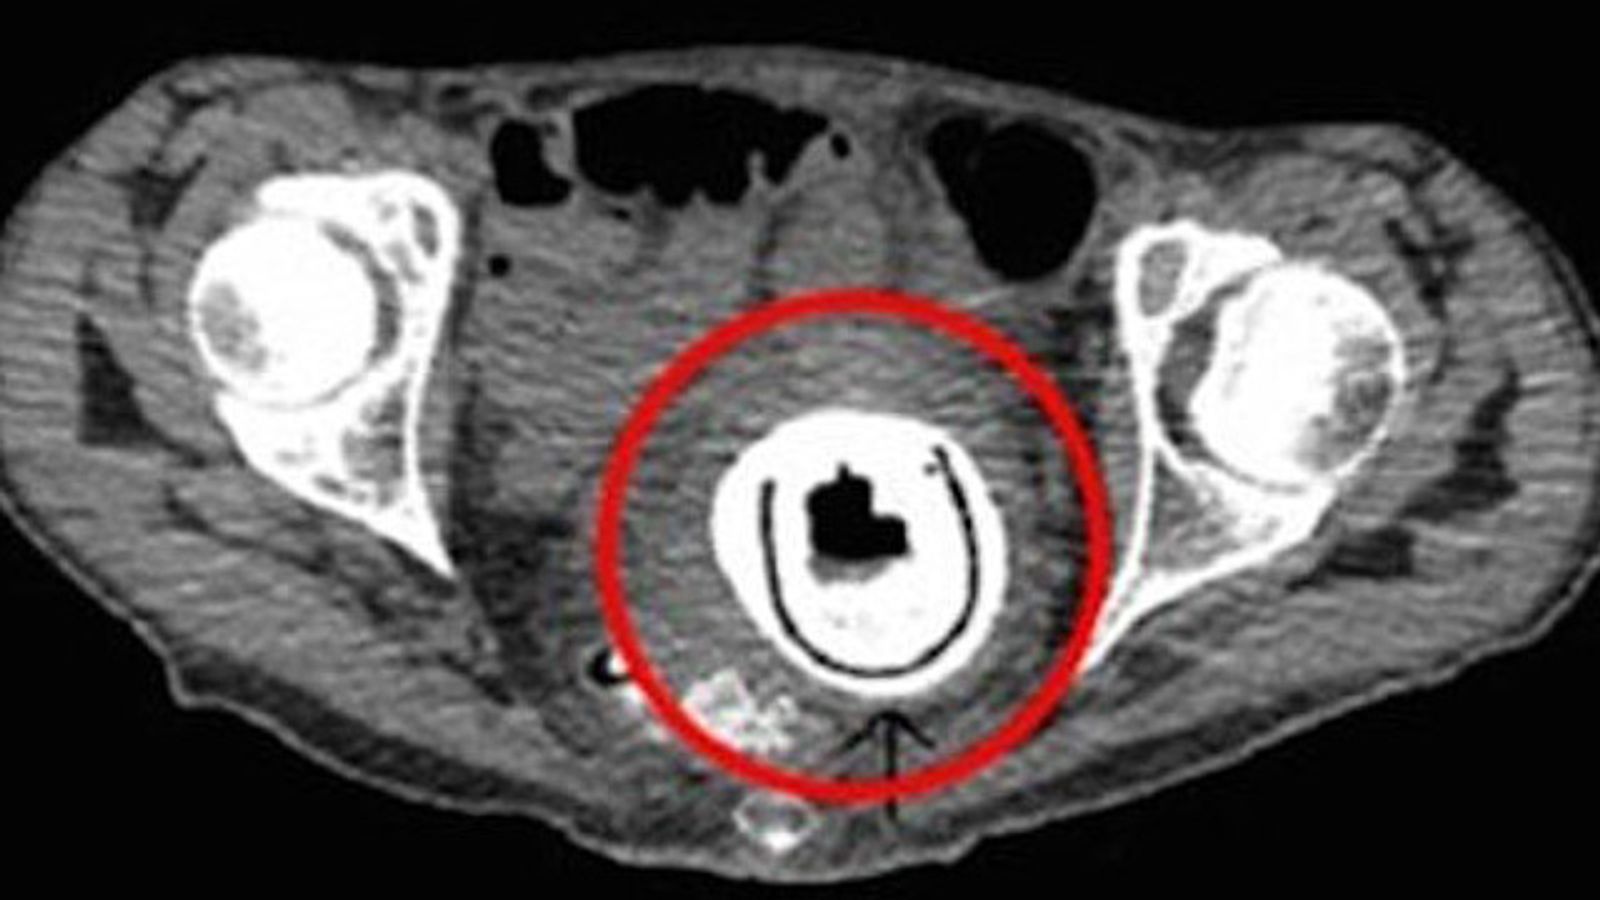

Woman Has Sex Toy Removed After It Spent Years In Her Vagina Avn pictures has 500 x 400 · 50 kB · jpeg.